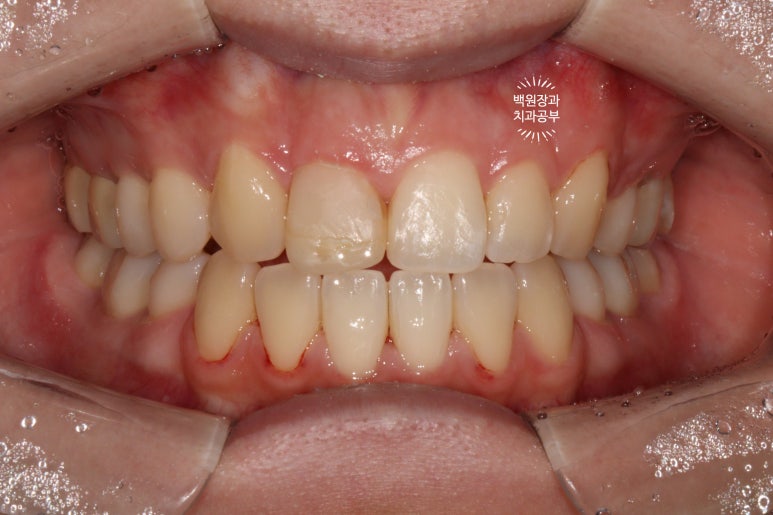

사실 전문가가 아니면 딱 보고 뭐가 문제지?? 라고 생각하실 수도 있을텐데요,

다시 보시면, 빨간색으로 표시된 것이 가장 가운데 치아인 중절치.

노란색으로 표시된 것이 작은 앞니인 측절치

파란색으로 표시된 것이 송곳니인 견치입니다.

마치, 가운데 앞니 두개가 모두 대문니 같아 보이지만, 하나는 레진으로 감싸놓은 착시 현상이라는 것!!

비교적 세모난 모양을 갖고 있는 송곳니의 위치를 파악하시고 나면, 아!!! 하고 깨달으실거에요. ㅎㅎ

전반적으로 A2.5~A3 shade를 갖던 치아들이, 2시간 정도 전문가 치아미백을 받고 나서

B1보다도 더 밝아졌답니다.

전반적으로 색조가 whitish하게 개선되었네요!